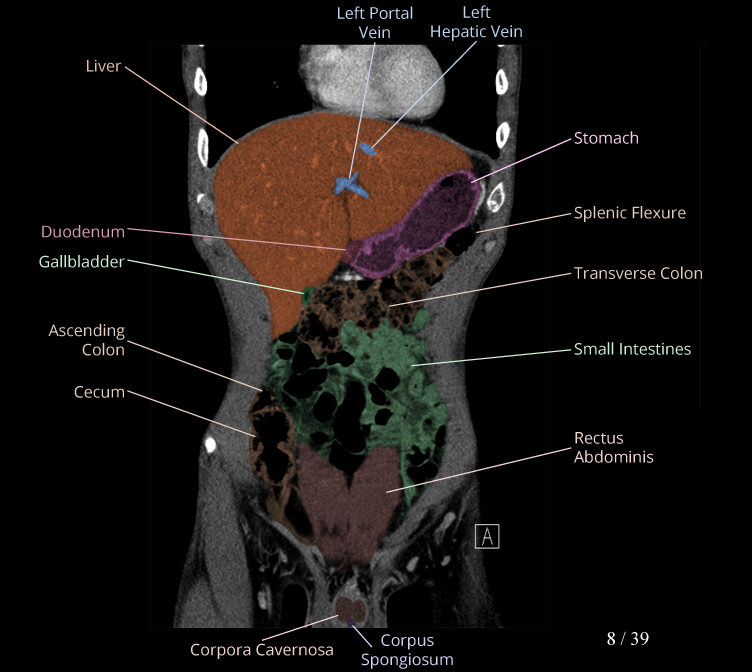

Body

Covers abdominal CT anatomy.